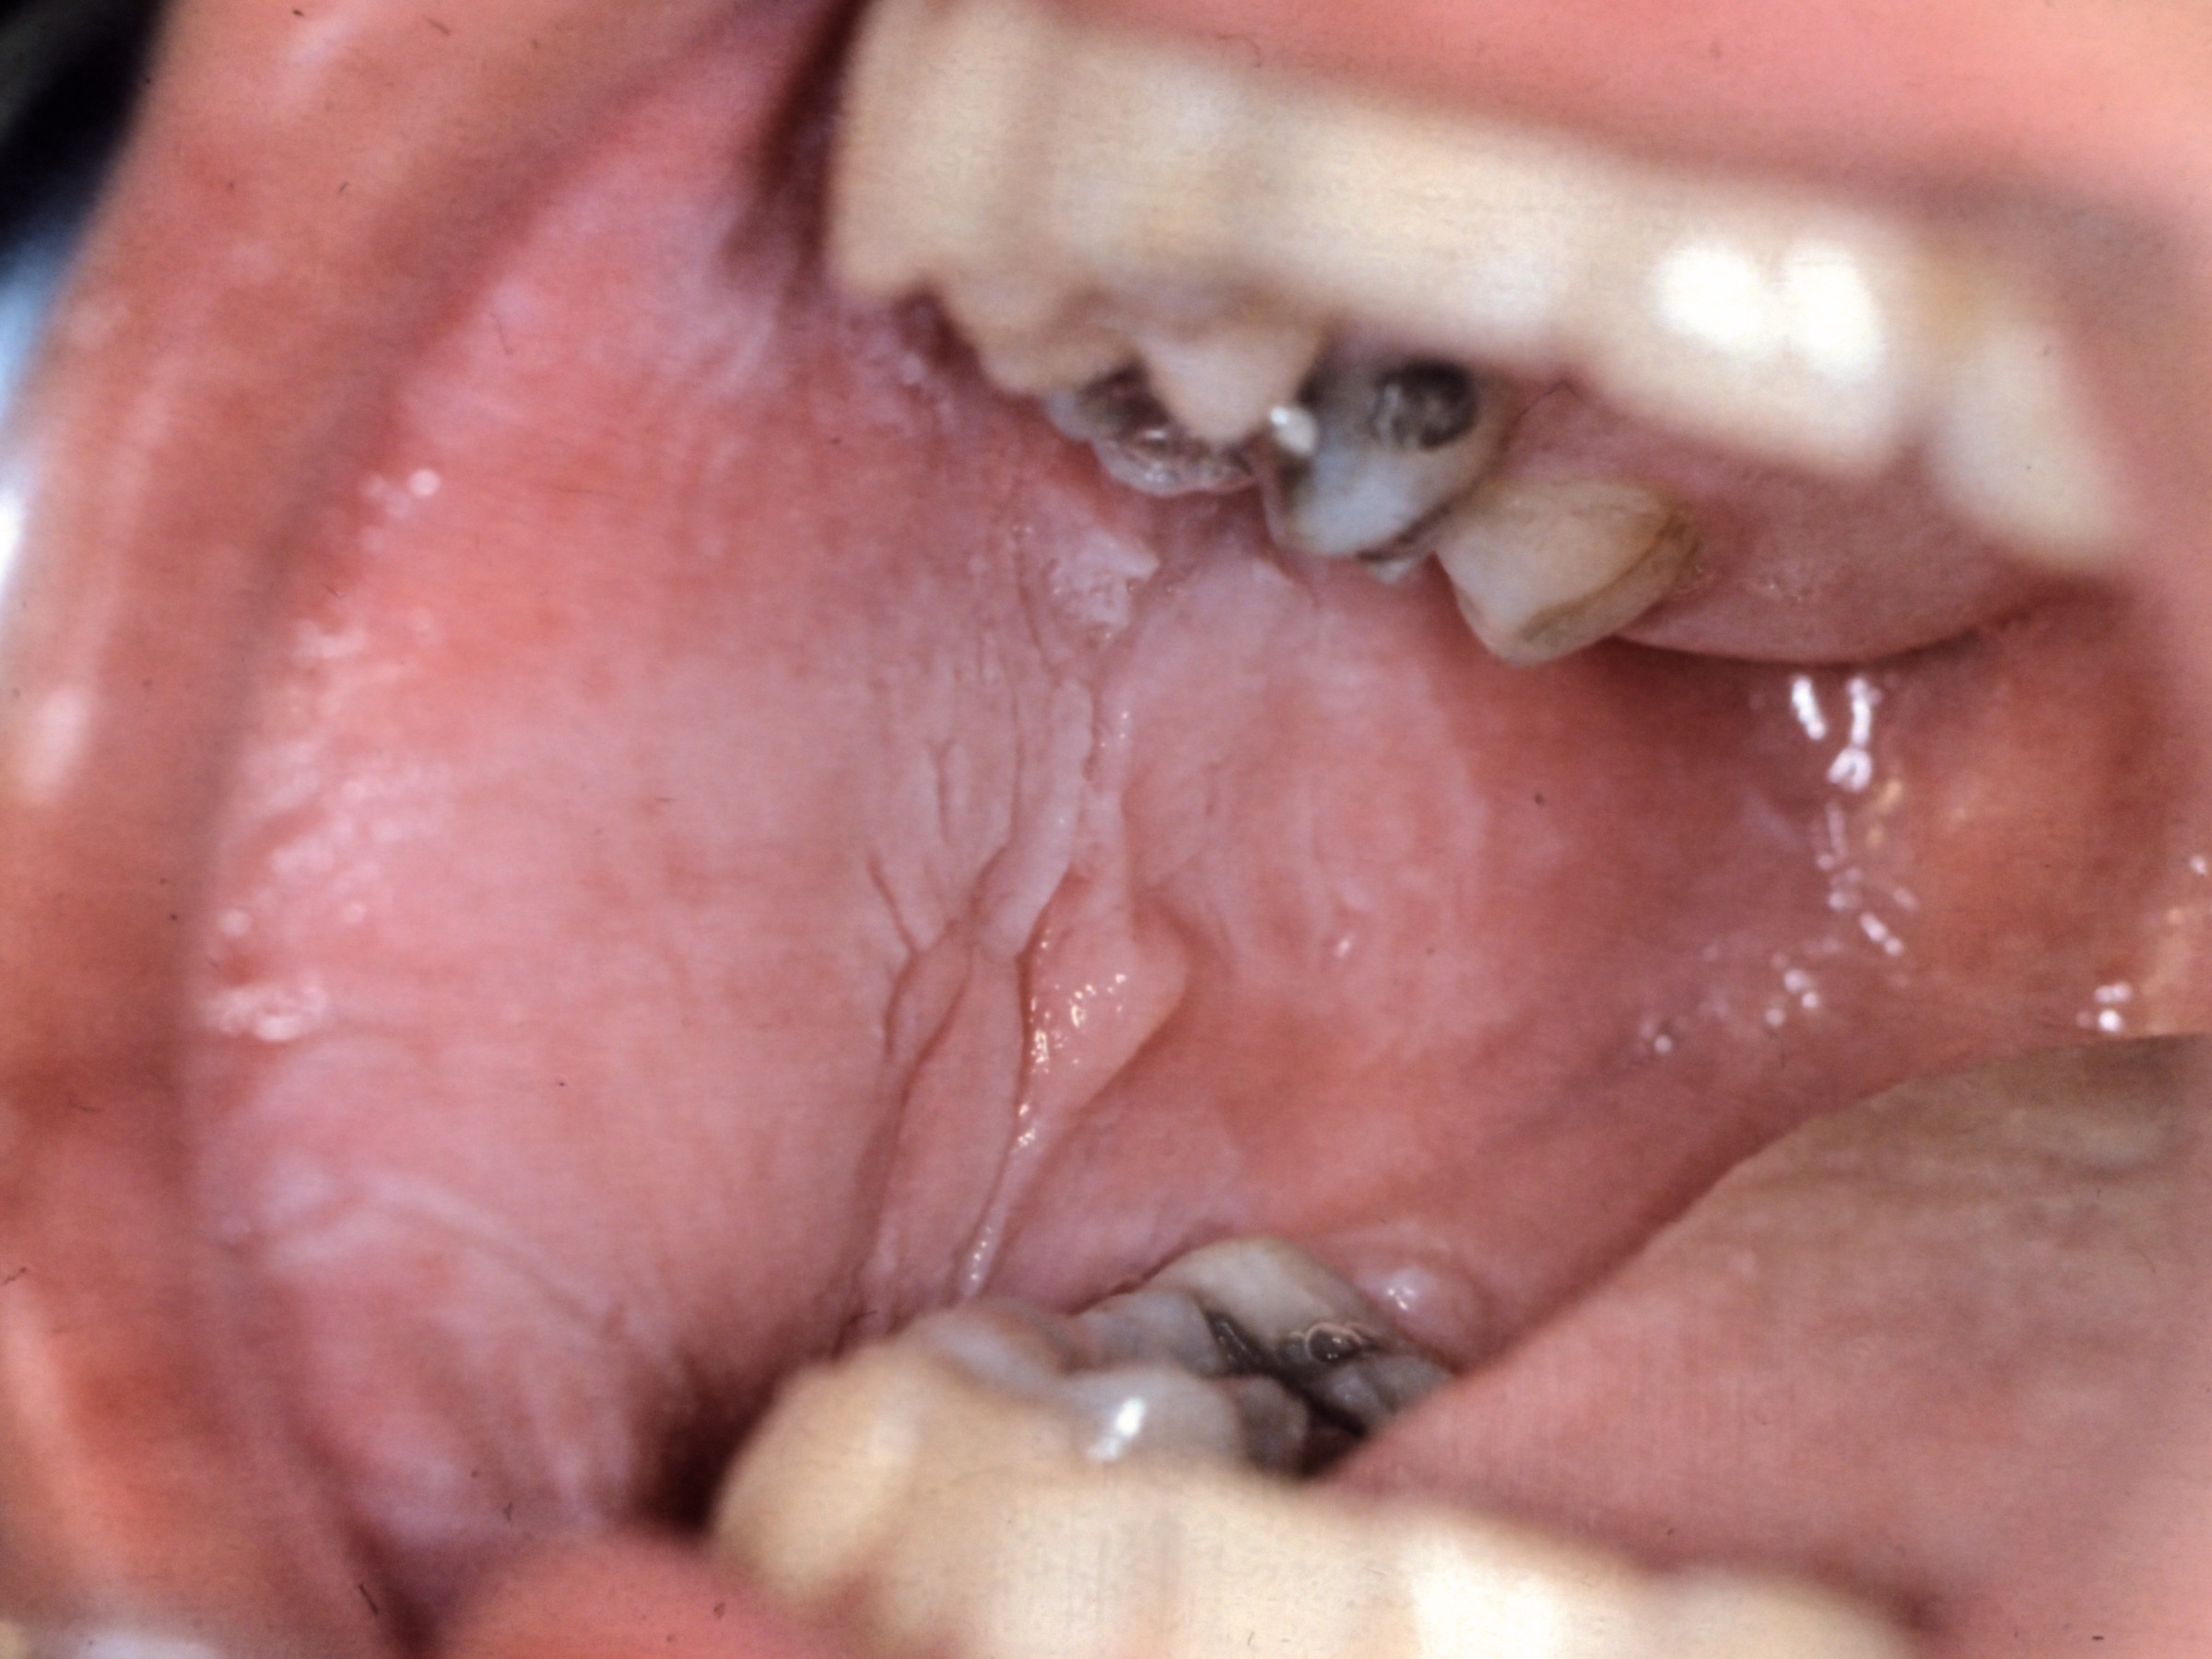

Klinisch beeld:Witte plaque, verkleuring

(leukoplakie) van het mondslijmvlies, meestal de tong of de tongrand. Andere

lokaties: overig mondslijmvlies, vooral de wangen, lippen, anaal slijmvlies, vagina-epitheel.

Onscherp of scherp begrensd. Soms kleine erosies. Vanaf de geboorte of kinderleeftijd

aanwezig, kan familiair voorkomen.

| white

sponge nevus |